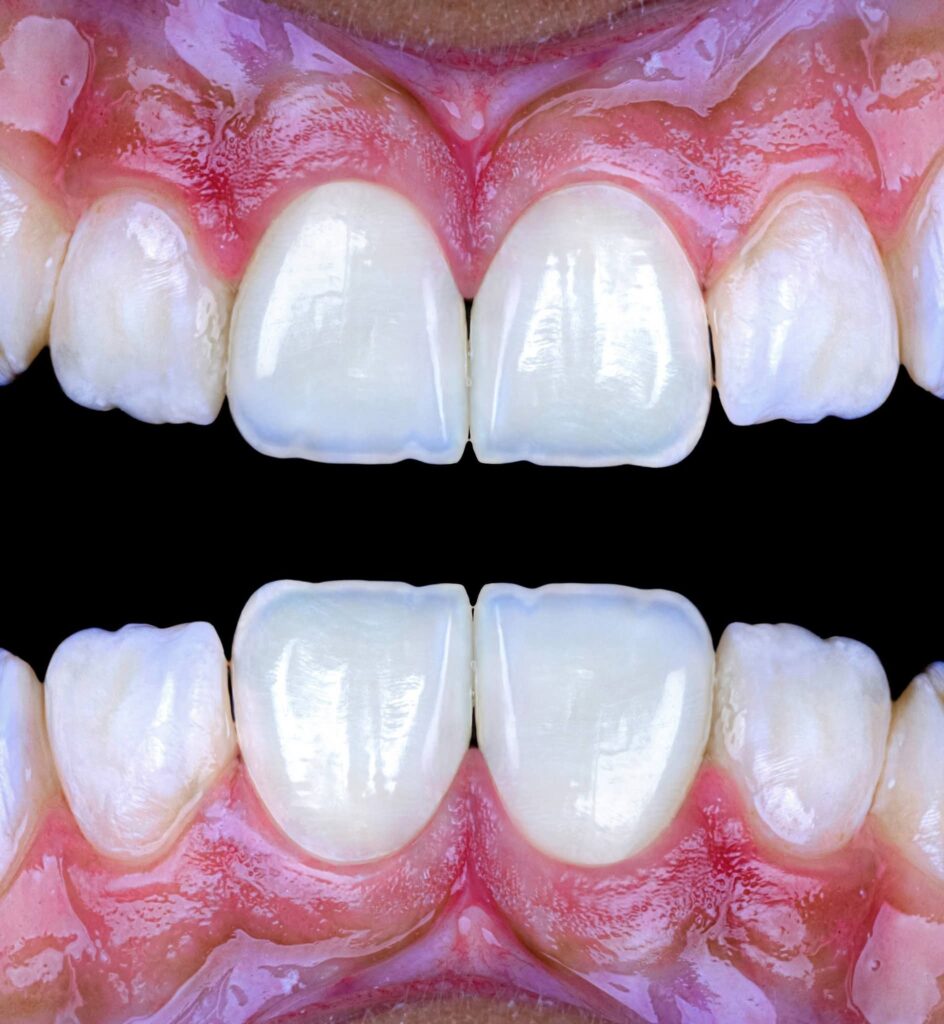

Symmetry refers to the mirror relationship between the right and left sides, especially the maxillary central incisors. Absolute symmetry is not always natural; therefore, perceived symmetry is more important than mathematical symmetry. Small differences in line angles, embrasures, and incisal edges can be used intentionally to create a natural appearance.

Proportionality relates to the width-to-length ratio and the relationship between anterior teeth. The ideal width/length ratio for central incisors is approximately 75–80%, and the apparent width proportion between anterior teeth often follows the golden proportion (~62%), although modern aesthetic dentistry prefers the concept of Recurring Esthetic Dental (RED) proportion for more natural results.

1. Tooth dominance (central incisors dominant)

Progressive embrasure increase from central to canine

2. Line angle positioning to control perceived tooth width

3. Surface texture and light reflection

4. Incisal translucency and halo effects